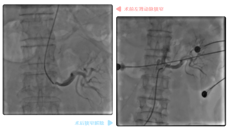

胸闷,多数人觉得“缓一缓”就好了,岂不知这是一个危险信号,尤其对40岁以上人群来说,因为这些表现极有可能跟您的心脏有关。 近日,71岁的岑大爷因胸闷住进了广西国际壮医医院心病科。当时他的症状严重到“闷到只能躺床上,一下地就头晕、恶心、想吐”。 经检查,心病科主任徐先增很快找到了胸闷的“元凶”——冠状动脉粥样硬化性心脏病(以下简称“冠心病”)。 对于冠心病,医生通常会以介入手术疏通狭窄血管,使其恢复供血...12.022021